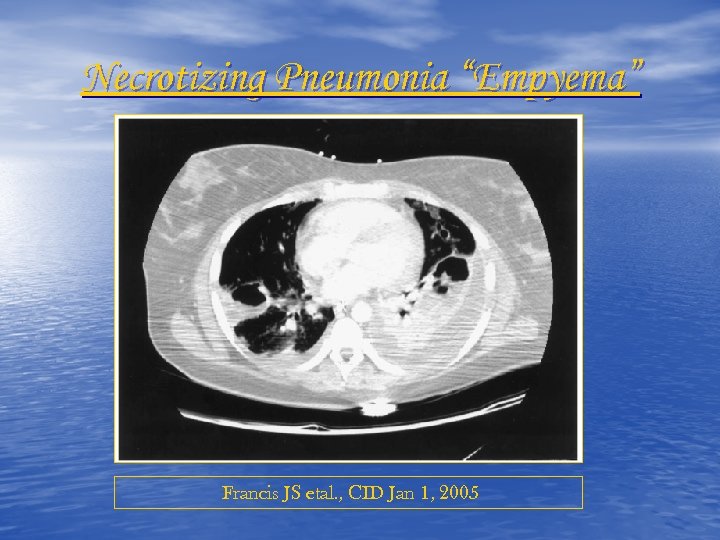

Necrotizing Pneumonia “Empyema” Francis JS etal. , CID Jan 1, 2005

Necrotizing Pneumonia “Empyema” Francis JS etal. , CID Jan 1, 2005